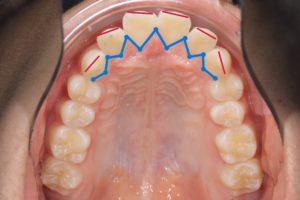

矯正治療前

赤い線が切端ライン

青い線が歯頚部ラインです。

抜歯後8カ月経過

唇側に向いていた切端ラインが

抜歯後内側(口蓋側)に向いています。

このように前歯を後退できるのは

精密検査時のCTデータで

骨の厚み、歯根の位置を立体的に把握し

前歯を下げても骨や歯肉に無理が生じないことを

事前に確認した上で治療を行うからです。